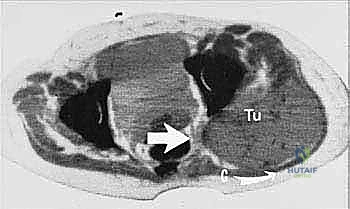

- التصوير المقطعي المحوسب (CT Scan): لتقييم مدى تدمير عظام الحوض وتحديد خطوط القطع الجراحي (Osteotomy lines).

يحرص الأستاذ الدكتور محمد هطيف على توثيق الخطوات الجراحية لضمان أعلى معايير الجودة الأكاديمية والطبية. توضح الصور التالية الدقة المتناهية في التعامل مع الأنسجة والأوعية الدموية أثناء الجراحة: